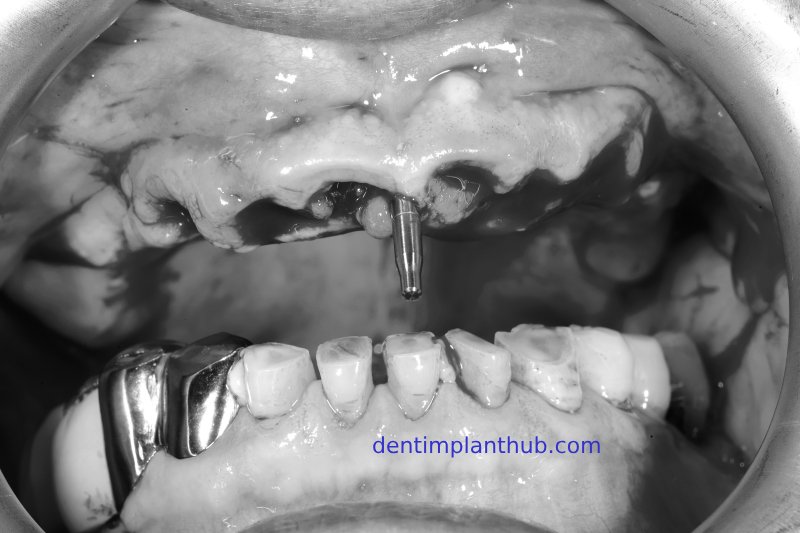

Photos taken during the implant surgery